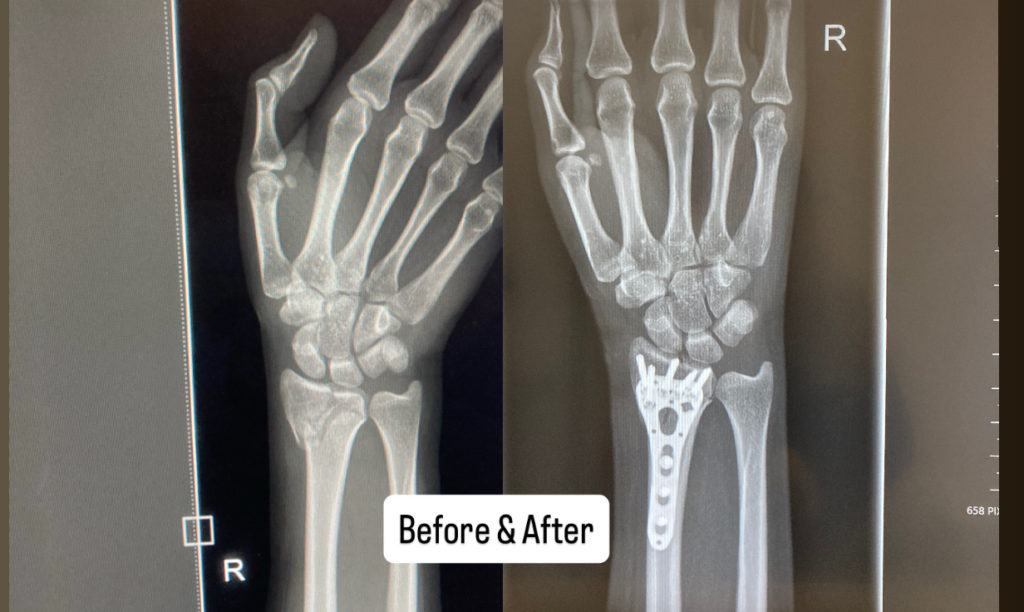

🧑⚕️「笑笑 手首を切開して、骨を元の位置に戻して、金属で固定するからね」

🧑⚕️「手のひら側のほうの手首」

昼の1時ごろに先生の問診が入り、経過は良好ですね。言われました。

今回トータルで3033ドルでした。

5000ドル以上を覚悟していたので、想像より安く少し安心しました。